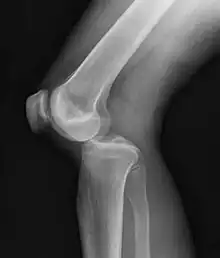

A lateral dislocation of the knee

They may be divided into five types: anterior, posterior, lateral, medial, and rotatory.[4] This classification is based on the movement of the tibia with respect to the femur.[11] Anterior dislocations, followed by posterior, are the most common.[2] They may also be classified on the basis of which ligaments are injured.[2]